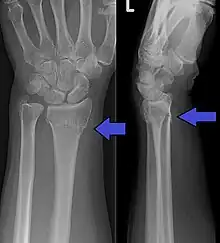

| An X-ray showing a Colles' fracture | |

Diagnosis can be made upon interpretation of anteroposterior and lateral views alone.[7]

The classic Colles fracture has the following characteristics:[8]

- Transverse fracture of the radius

- 2.5 cm (0.98 inches) proximal to the radio-carpal joint

- dorsal displacement and dorsal angulation, together with radial tilt[9]

- Radial shortening

- Loss of ulnar inclination

- Radial angulation of the wrist

- Comminution at the fracture site

- Associated fracture of the ulnar styloid process in more than 60% of cases.